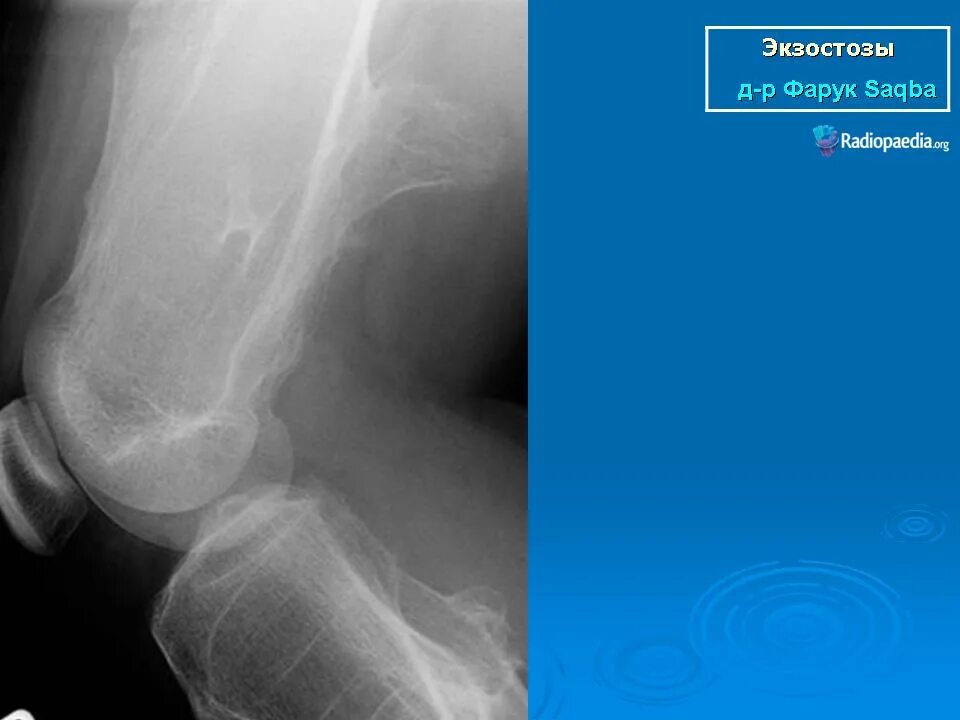

Экзостоз мкб 10